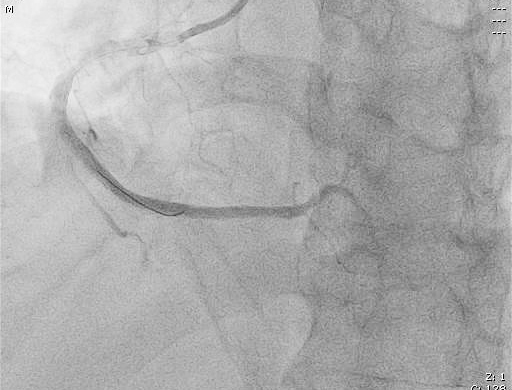

患者進(jìn)入導(dǎo)管室后,憋喘明顯,血壓、氧飽和度低,需面罩吸氧、大劑量去甲腎上腺素維持血壓。朱宗濤主任建議應(yīng)使用強(qiáng)支撐指引導(dǎo)管,先用軟導(dǎo)絲輕柔操作,結(jié)合血管內(nèi)超聲(IVUS),嘗試尋找血管真腔。術(shù)中選擇6F SAL指引導(dǎo)管行冠狀動(dòng)脈造影提示右冠中段閉塞,先后嘗試Anyreach、Sion工作導(dǎo)絲未能通過(guò)閉塞病變,然后在Finecross微導(dǎo)管輔助下,換用Gaia1硬導(dǎo)絲通過(guò)閉塞處成功送至右冠遠(yuǎn)端,行血管內(nèi)超聲(IVUS)檢查顯示血管支架遠(yuǎn)段局部夾層、血腫,導(dǎo)絲全程位于血管真腔,在IVUS精確定位下,成功開(kāi)通血管并植入支架2枚。術(shù)后,經(jīng)CCU醫(yī)護(hù)人員的精心治療,已于10月10日康復(fù)出院。

術(shù)后